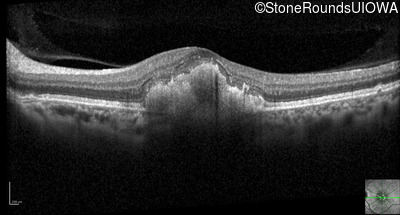

Optical Coherence Tomography - Right - 20/40 -1

Exemplar / OCT Stack